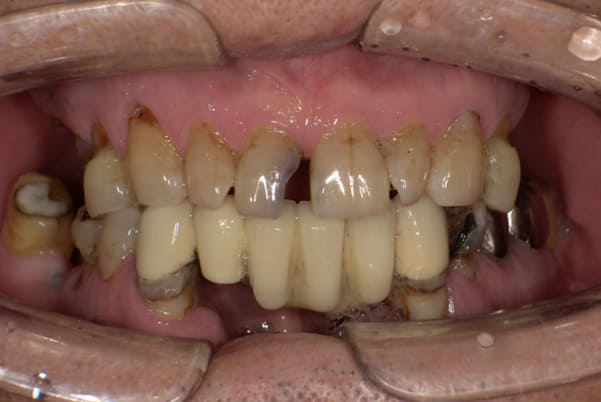

上の前歯が重度歯周病により動揺し、残せない状態のため、入れ歯も動揺がありました。

ご自身の歯に負担の少ないバネ、また見た目も改善

バネをかける歯は繋げることで強度を増し、歯への負担を軽減し、歯の寿命を長くする設計へ。

バネがかかる歯の被せ物は、歯への負担を減らし、入れ歯が動きにくいようになる形態をあらかじめ付与することで、より入れ歯の機能が高まります。

治療を行う際、被せ物や入れ歯は、別々に考えるのではなく、一口腔単位としてお口全体のことを考え最良の治療計画を立てることが歯の寿命、機能効果を向上させるため、専門医としてこのことは常に心掛けて治療を行っています。

治療前は上下奥歯の入れ歯が削れていることで、かみ合わせが低くなり唇もつむった状態でした。

かみ合わせを適切な高さに戻したことで、本来の自然な口元へ。